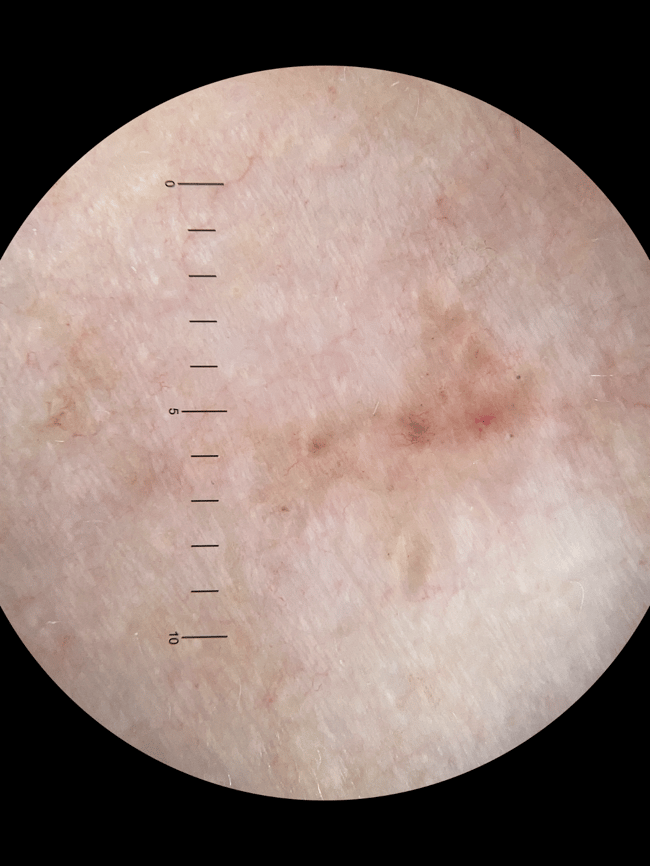

Case discussion: A lesion found on the left anterior shoulder of a 60-year-old female. What would you do next?

This week we revisit a case submitted by Dr Leanne Drew. A 60-year-old female patient presents for her annual skin check with no specific concerns.

This lesion is found on her left anterior shoulder. What do you think of it?